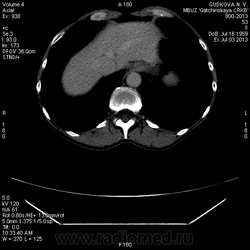

МСКТ брюшной полости с болюсом контраста. Образование правой доли печени, интенсивно накапливающее контраст в арт. фазу. Что это???

Сегодня, 3.07.13., выполнена МСКТ органов брюшной полости с болюсным контрастированием (омнипак-300 - 100 мл) на программе "3 фазы печени"

На преконтрастной серии - впечатление о расширении нижней полой вены.

В артериальную фазу - интенсивное накопление контраста, как раз в области этого расширения, в 4-5 сегментах печени.Выше и ниже - идет неизмененная НПВ, без контраста (фаза артериальная!) В венозную фазу - небольшая гиперденсная зона перикавально в печени - и все.

Этот участок патологического накопления контраста имеет размер 2,5 * 2,5 см, никак не 1,1 * 1,1(как дают УЗИ-сты)